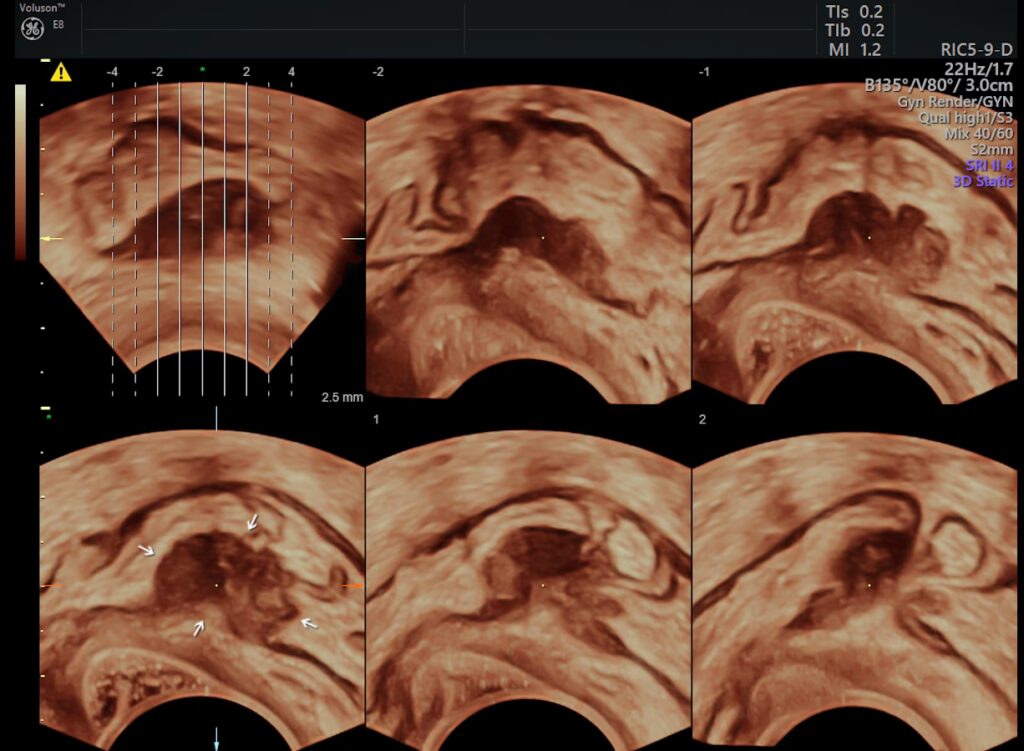

For at forstå sammenhængen er det vigtigt først at have en klar definition af endometriose. Endometriose er en tilstand, hvor væv, der ligner livmoderslimhinden (endometriet), vokser uden for livmoderen. Dette væv kan sætte sig på æggestokkene, æggelederne, ydersiden af livmoderen, tarmene eller andre organer i bækkenområdet. Hver måned reagerer dette fejlplacerede væv på de hormonelle cyklusændringer på samme måde som slimhinden inde i livmoderen: det fortykkes, nedbrydes og bløder. Men i modsætning til menstruationsblod har dette blod ingen vej ud af kroppen. Dette fører til en kronisk inflammatorisk reaktion, som kan forårsage arvæv, cyster (kendt som endometriomer eller 'chokoladecyster') og sammenvoksninger, der kan føre til stærke smerter og infertilitet.